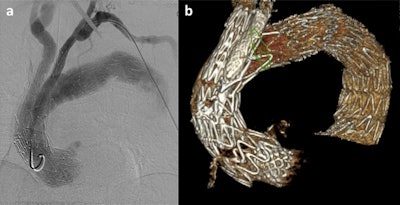

Whether performing a complex or more straightforward procedure, surgical teams need x-ray guidance to position the endograft correctly in the patient's aortic anatomy, and advanced imaging techniques are being used in operating rooms that are now hybrid rooms combining the best of advanced imaging with the best of open surgery, Haulon continued.

He pointed to fusion guidance being a way to have 3D guidance when registering the preoperative CT scan on top of the fluoroscopy image. This helps with accuracy, reducing exposure to radiation and using less contrast. Conebeam CT performed at the end of the procedure provides a 3D data set that doctors can use to check technical success -- if there are any issues, these can be fixed right away, he noted.

The hospital's first 3D-printed aorta was produced in 2019, and it was for a patient with an aortic iliac aneurysm. Following preoperative CT angiography, the surgical team sized the endograft and prepared the fusion mask for intraprocedural guidance, and then extracted the DICOM file of the aorta and converted it into an STL file, which is a format native to the stereolithography CAD software created by 3D systems. From this file, the model was printed. The first simulation was deemed similar to a classic procedure and much better than commercially available endovascular simulators, according to Haulon.